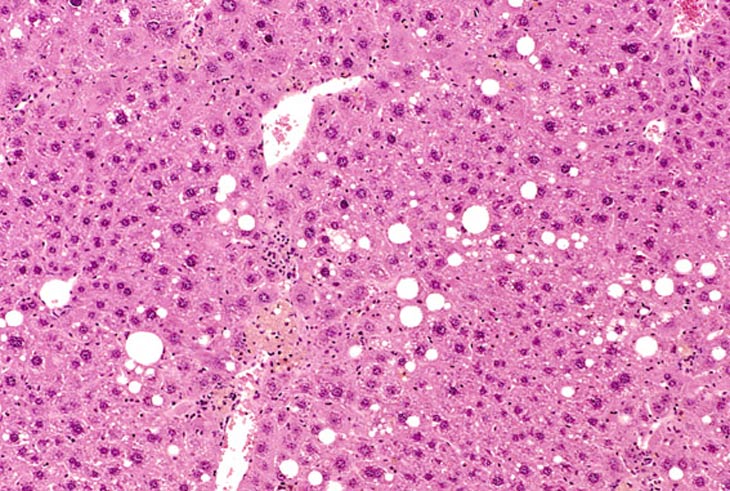

Fatty change and pigment accumulation within Kupffer cells along with proliferation of sinusoidal lining cells are features of toxic change in this liver.